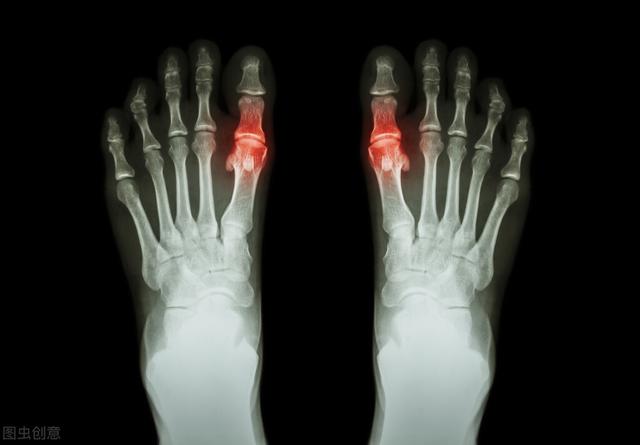

痛風かどうかを判断する方法は、主に関節による。53%から70%の患者の発症当初は、第一趾の関節(足痛風と呼ばれる)が赤く腫れ、熱く痛み、通常は多発し、一部は複数の関節として現れることもある。固定性、非対称性で、次第に足首、膝、手首、肘などの大きな関節に浸潤することもある。

第2段階は、例えば超音波検査で「ダブルトラックサイン」を検出したり、画像検査を行うことである。デュアルエナジーCTで尿酸塩沈着が見つかるなど、そしてX線検査で軟部組織の腫脹、軟骨辺縁の破壊、関節面の不整が認められる。!

痛風の典型的な症状は、関節が赤く腫れ、熱く痛むことである。 最もよく罹患する関節は母趾(医学用語:第一中足骨)で、その他に足関節、膝関節、肘関節によく見られる。症状は夜間に突然現れることが多い。病院での検査は主に血中尿酸のチェックです。しかし、痛風発作が起きても尿酸値が高くない患者もいるので注意が必要である。やはり病院で検査を受け、標準的な治療を受けることをお勧めします。外来では、鎮痛剤の自己乱用が腎不全につながるケースがよく見られますが、これは非常に残念なことです。さらに、高尿酸血症の患者全員が痛風を発症するわけではなく、他のリスクもあるため、ある程度の高尿酸血症は薬物療法でコントロールする必要がある(掲載した見出し記事参照)。

痛風の急性発作では、しばしば罹患した関節(最も一般的なのは母趾と足背)に著しい局所の発赤、腫脹、熱感、疼痛、機能障害がみられる。

5.第1中足趾節関節の発作:上図のこの関節に発赤、腫脹、痛みの発作があれば、上記の2、3、5を同時に満たすと考えられるので、この関節の発作は痛風と診断される確率がかなり高くなる;

- (5) 第1中足趾節関節(足の母趾)の痛みや腫れ

- (6) 片側の第1中足趾節関節病変

5.第1中足趾節関節(足の母趾)の痛みや腫れ

第1中足趾節関節(赤色

6.片側第1中足趾節関節病変